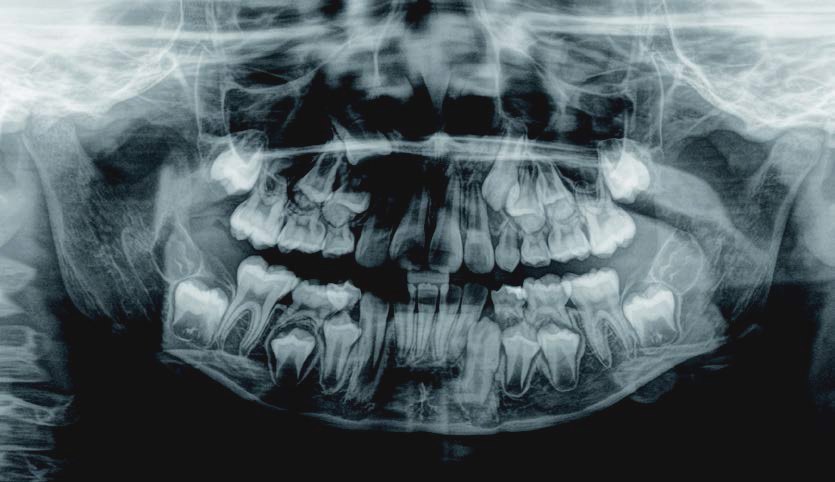

歯がガタガタに並んでいて、前歯の真ん中の位置が少し左にずれていました。

奥歯が生えるためのスペースが足りず、永久歯が生えて来られない状況が確認できました。

また、飲み込むとき下くちびるに力が入ってしまうクセが見られ、お顔全体の成長が遅れている様子が確認できました。